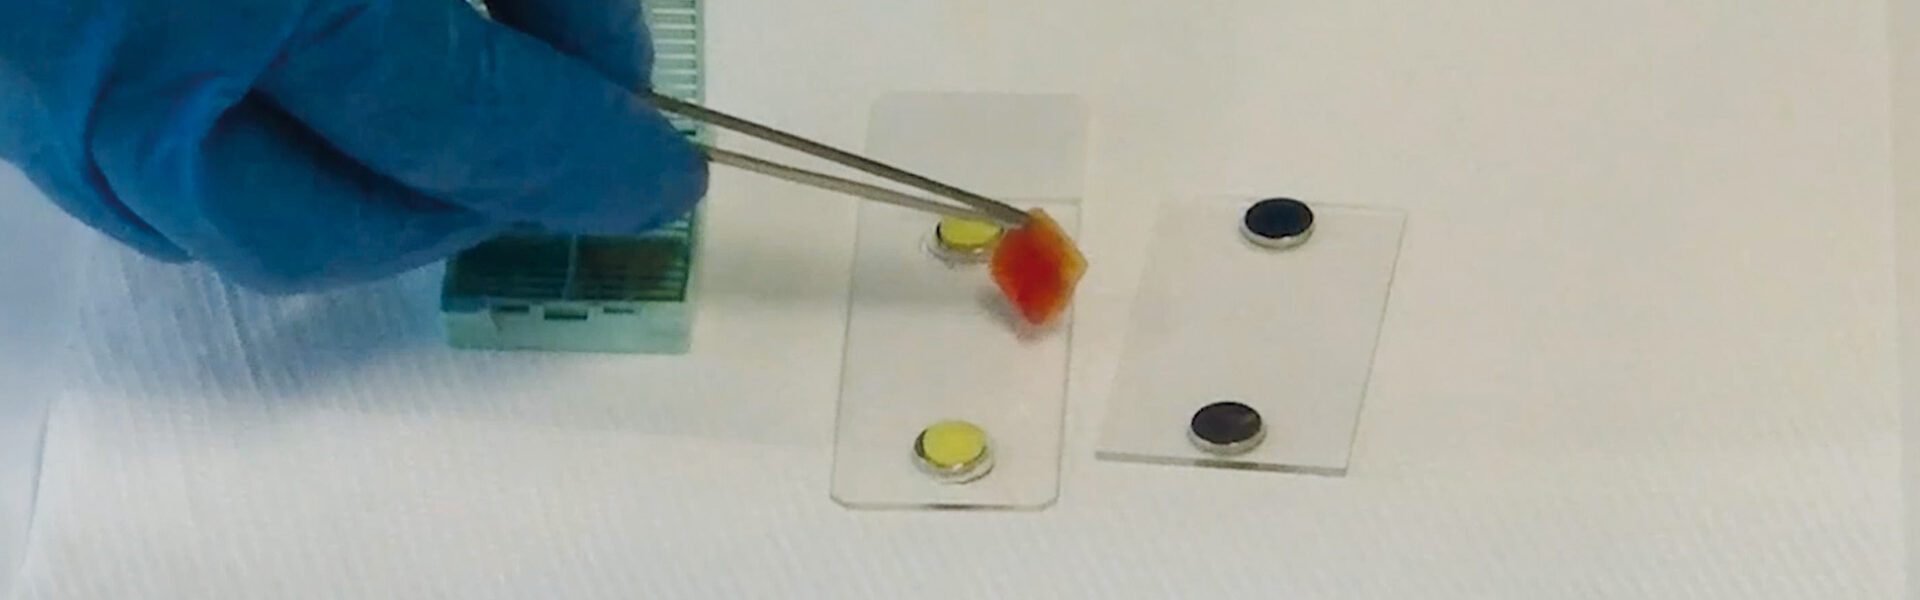

Minimal preparation & direct assessment

Tissue integrity

The VivaScope 2500 rapidly scans the excised tissue and reveals the cellular morphology right at the bedside. The examined tissue remains unharmed by the procedure and can be preserved for later histopathological analysis.

Full Preservation.

The VivaScope 2500 revolutionizes the evaluation of cytological and microhistological specimens. The analysation and adequacy assessment of these samples can be rapidly performed while maintaining the integrity of the specimen for subsequent histological, immunohistochemical and molecular analysis.